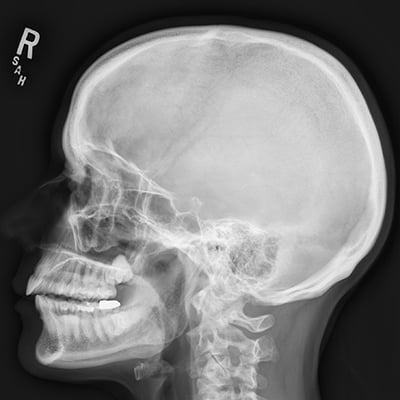

This module will help you achieve optimal images when performing examinations of the skull, facial bones, orbits, and nasal bones. Patient preparation and positioning are discussed, as well as technical settings and patient instructions. Descriptions and images of the expected anatomical structures are included, as well as image evaluation criteria.